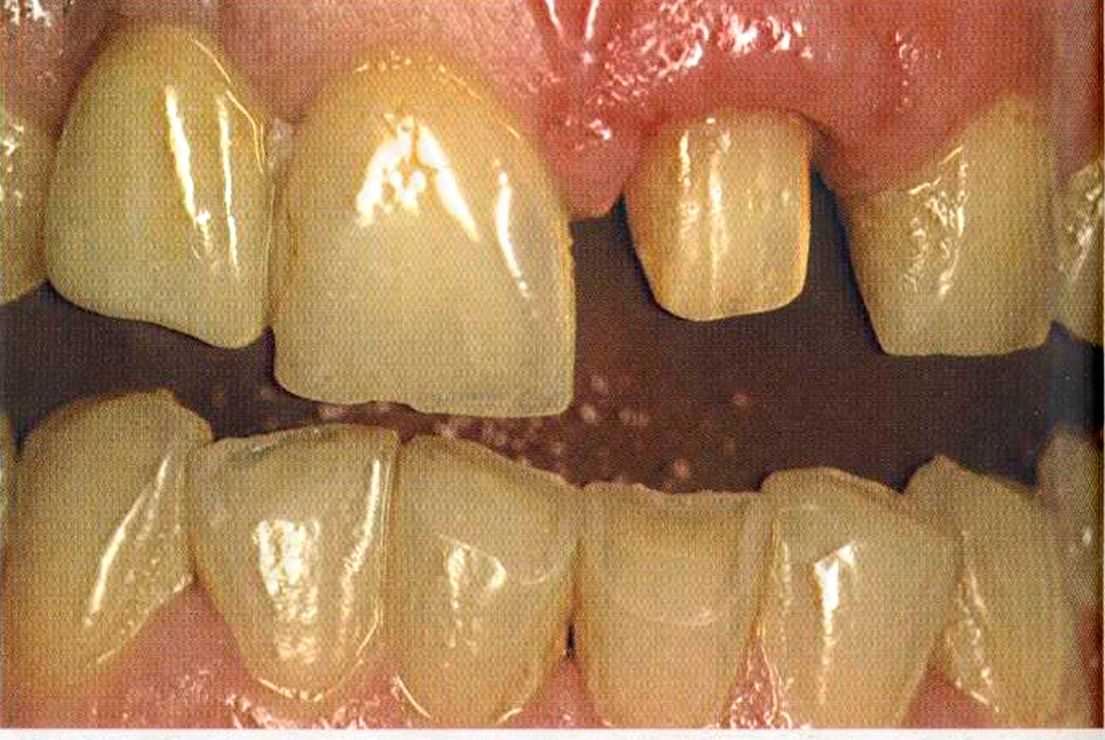

Этот пациент — португалец. Он всю жизнь имел такое положение зубов. Небнорасположенный боковой резец теперь необходимо удалить, а затем воссоздать как эстетику, так и функцию в области фронтальной группы зубов. Планируется изготовить коронки In-Ceram в области 11 и 21 и соединить их вместе из-за увеличивающейся подвижности зубов.

Препарирование, проводимое доктором Риссе, оценивается как очень сложное. Режущие края центральных резцов сильно дивергируют, что создает неудобство при формировании хорошего уступа.

Из-за сильной протрузии центральных резцов на них всегда падает итого света, и они кажутся очень большими. Чтобы смягчить этот эффект, мы выбрали более темный цвет для реставрации.

Фото сверху и слева: отличный результат препарирования зубов с уже уложенными нитями для снятия оттиска.

Готовая работа привела в восторг нашего пациента. Он даже не мог себе представить, что соединенные вместе коронки могут выглядеть так естественно. Мы решили не копировать на реставрацию белое пятно, имеющееся на 12 зубе.